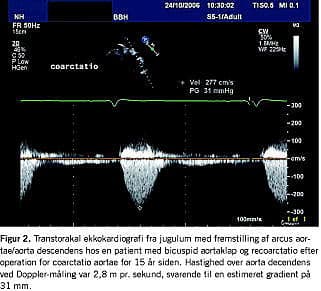

Associeret kardiovaskulær malformation ses hos op mod 20% af patienterne med BAK. Eksempler herpå omfatter coarctatio aortae, ventrikelseptumdefekt og persisterende ductus arteriosus. Coarctatio aortae er associeret med BAK i mere end 50% af tilfældene (Figur 2 ), og kombinationen giver en særlig risiko for aortadissektion [22, 24]. 15-18% af patienterne med Turners syndrom har BAK [25]. BAK har generelt en veludtalt hereditær komponent, der er forenelig med autosomalt dominant arvegang med varierende penetrans [1]. Resultaterne af nyere studier har dog peget mod en mere kompleks og heterogen arvelighed som basis for den familiære ophobning [26].